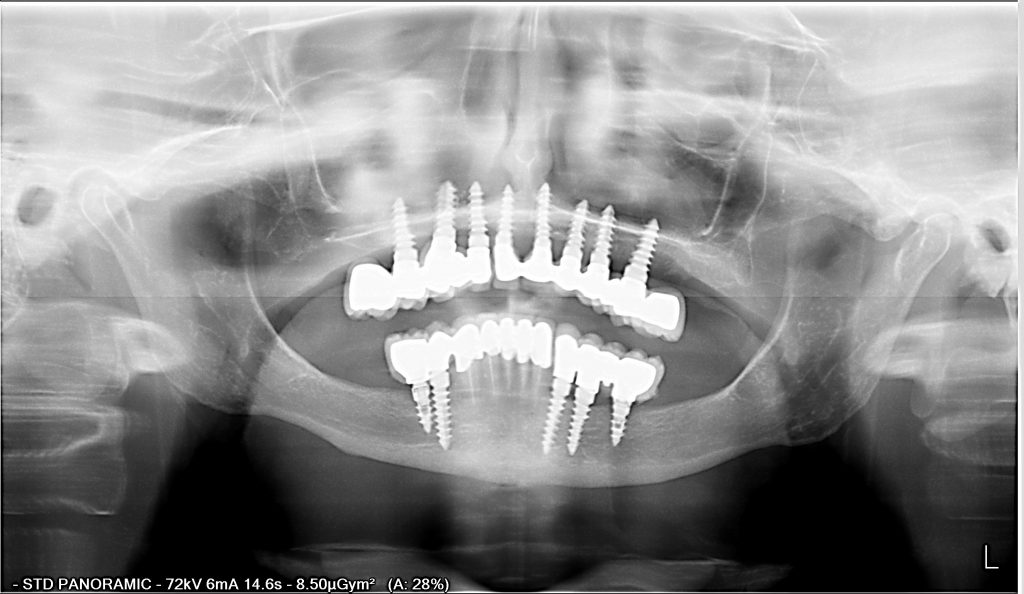

RECONSTRUCTION DENTAIRE INFERIEURE ET SUPÉRIEURE PAR IMPLANTS DENTAIRES

Reconstruction supérieure et inférieure. 12 couronnes céramo-métal sur 8 implants dentaires à chaque mâchoire. Chirurgien spécialiste en implant dentaire: Dr. Thierry Hascoet. Prosthodonte: Dra. Yanira Peña. Laboratoire: Rubén Escola.